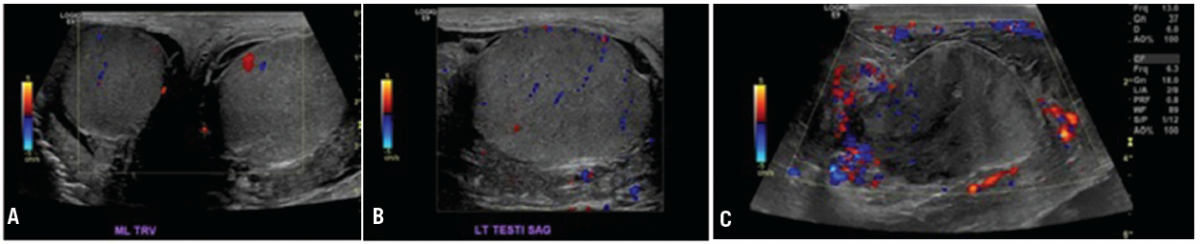

Figure 1. A. Ultrasound on admission showed an enlarged left testicle, hypoechoic left hydrocele, and mild left scrotal wall thickening with no evidence of torsion. B. Ultrasound on admission shows normal appearing left testicle with adjacent hydrocele. C. Repeat ultrasound 5 days after admission now showed hypoechoic areas within the left testicle.

Over the next few days, the patient reported no decrease in his pain. His leukocytosis worsened during his stay and he developed fevers. Ultrasound was repeated and changes were noted (Figure 1). There were new hypoechoic areas within the left testicle, and the hydrocele had more of a phlegmon-type appearance. A left scrotal exploration was done. A fair amount of phlegmon and fibrinous materials with a grossly abnormal appearance of the left testicle and epididymis was encountered.